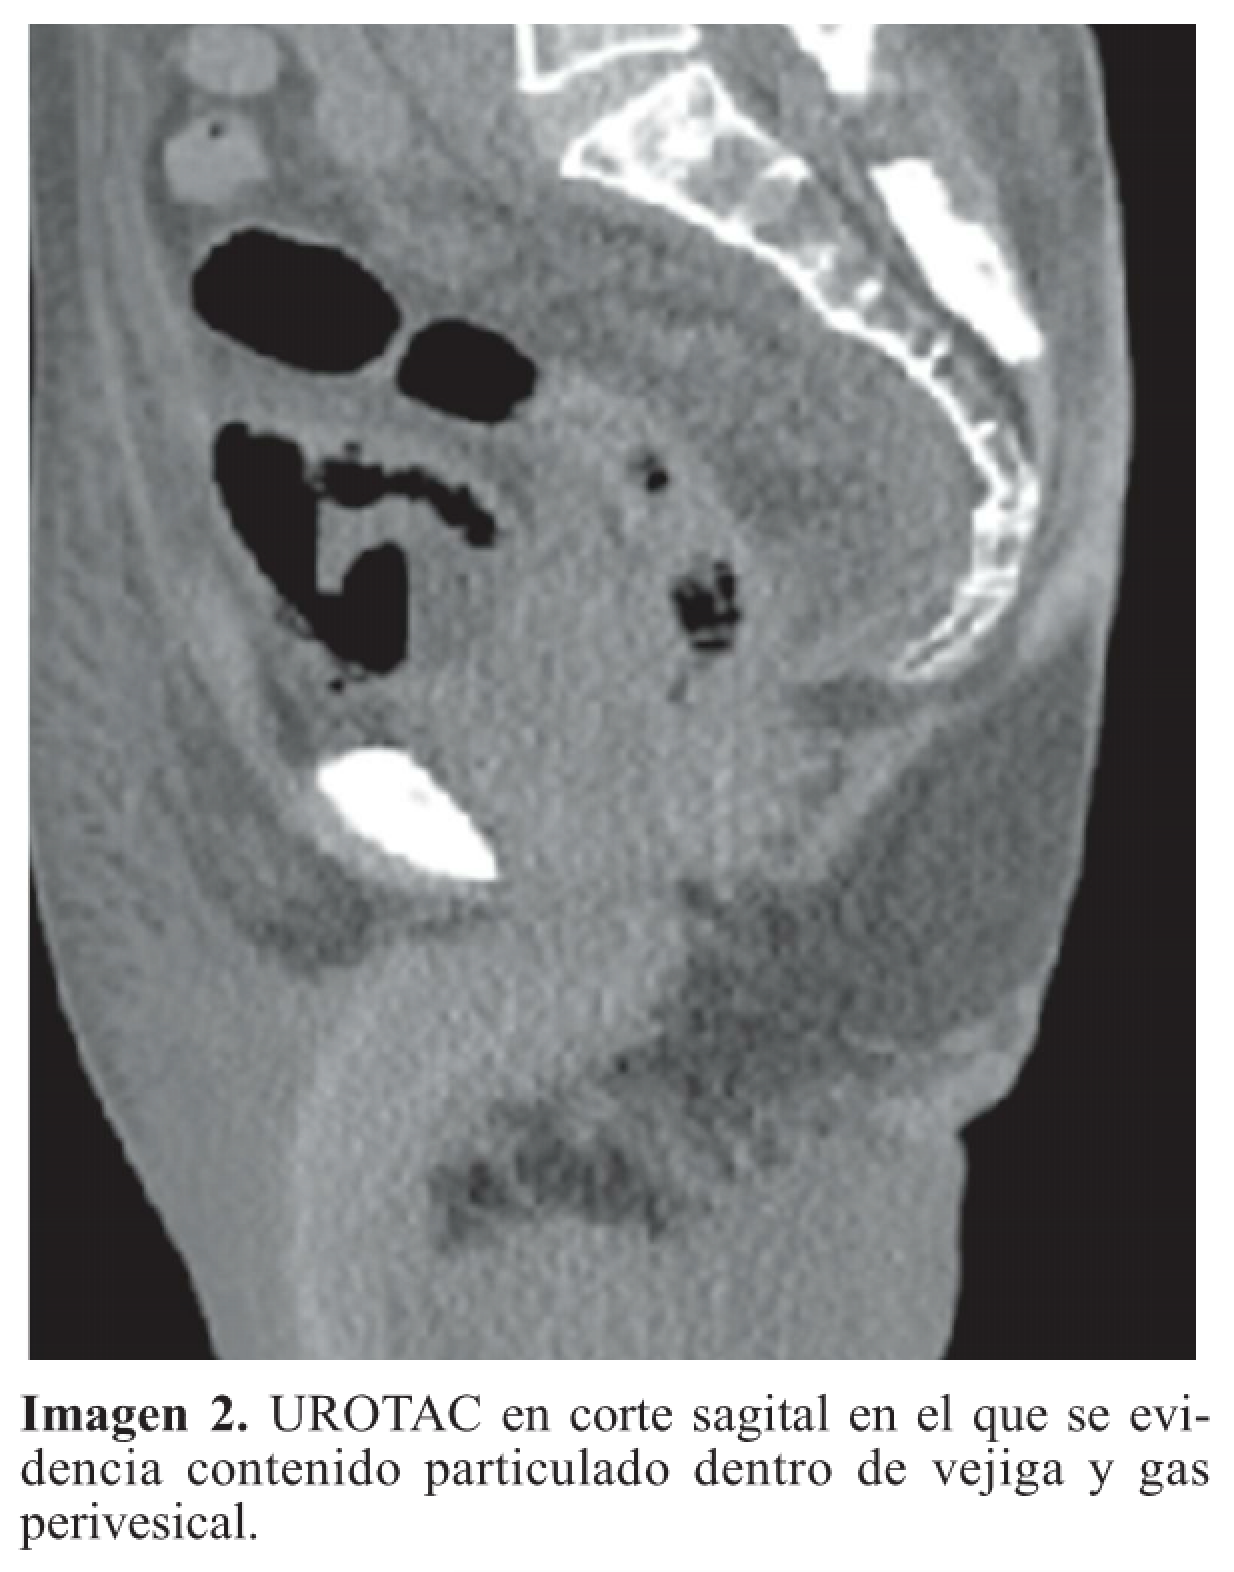

Se recibe reporte de patología, el cual evidencia tumor neuroendocrino tipo células de Merckel; entonces se valora por Oncología, donde indican inicio de quimioterapia ambulatoria, una vez se dé el egreso hospitalario. Una semana después el paciente presenta hematuria franca y oliguria; en estudios de laboratorios evidencian uroanálisis con hematuria, proteinuria en rango nefrótico y sedimento activo, con función renal dentro de parámetros de normalidad. Dados los nuevos hallazgos clínicos y el antecedente de diabetes, se decide solicitar estudios adicionales, descartando por oftalmología retinopatía diabética; adicionalmente el equipo de Nefrología descarta síndrome nefrótico, al evidenciar orina de 0,3 g en 24 horas, hipoalbuminemia y perfil lipídico normal; así mismo la morfología globular se encontraba en el 60% de hematíes eumorfos, descartando glomerulopatías. Investigando el origen de la hematuria, se complementa con estudios anatómicos; en efecto, se inicia con ecografía de vías urinarias que reportan buena diferenciación corticomedular con riñones conservados de tamaño; posteriormente se solicita UROTAC para observar el tracto urinario bajo, evidenciándose engrosamiento de la pared vesical, gas perivesical como se observa en las imágenes 1, 2 y 3, y con conglomerados ganglionares retroperitoneales, hallazgos compatibles con cistitis enfisematosa.

El caso aquí reportado se correlaciona con lo encontrado en la literatura desde el punto de vista del aislamiento microbiológico que corresponde a una Escherichia coli, aunque el nuestro es una E. Coli con patrón de resistencia a betalactamasas de espectro extendido (BLEE), probablemente por las complicaciones anotadas, como la hospitalización previa para el manejo posoperatorio del colgajo de piel y el uso de antibióticos en dicha hospitalización. También, se correlaciona con la literatura en la presentación del cuadro clínico, el antecedente de diabetes como el factor de riesgo más  asociado, y  en el abordaje diagnóstico, en el cual se pudo documentar el aire perivesical por medio del UROTAC, que es el examen con mayor sensibilidad y especificidad para el diagnóstico de esta patología.